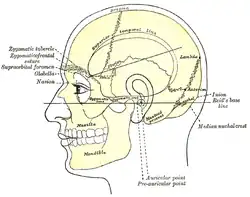

| Side view of head, showing surface relations of bones. (Mastoid process labeled near center.) | |